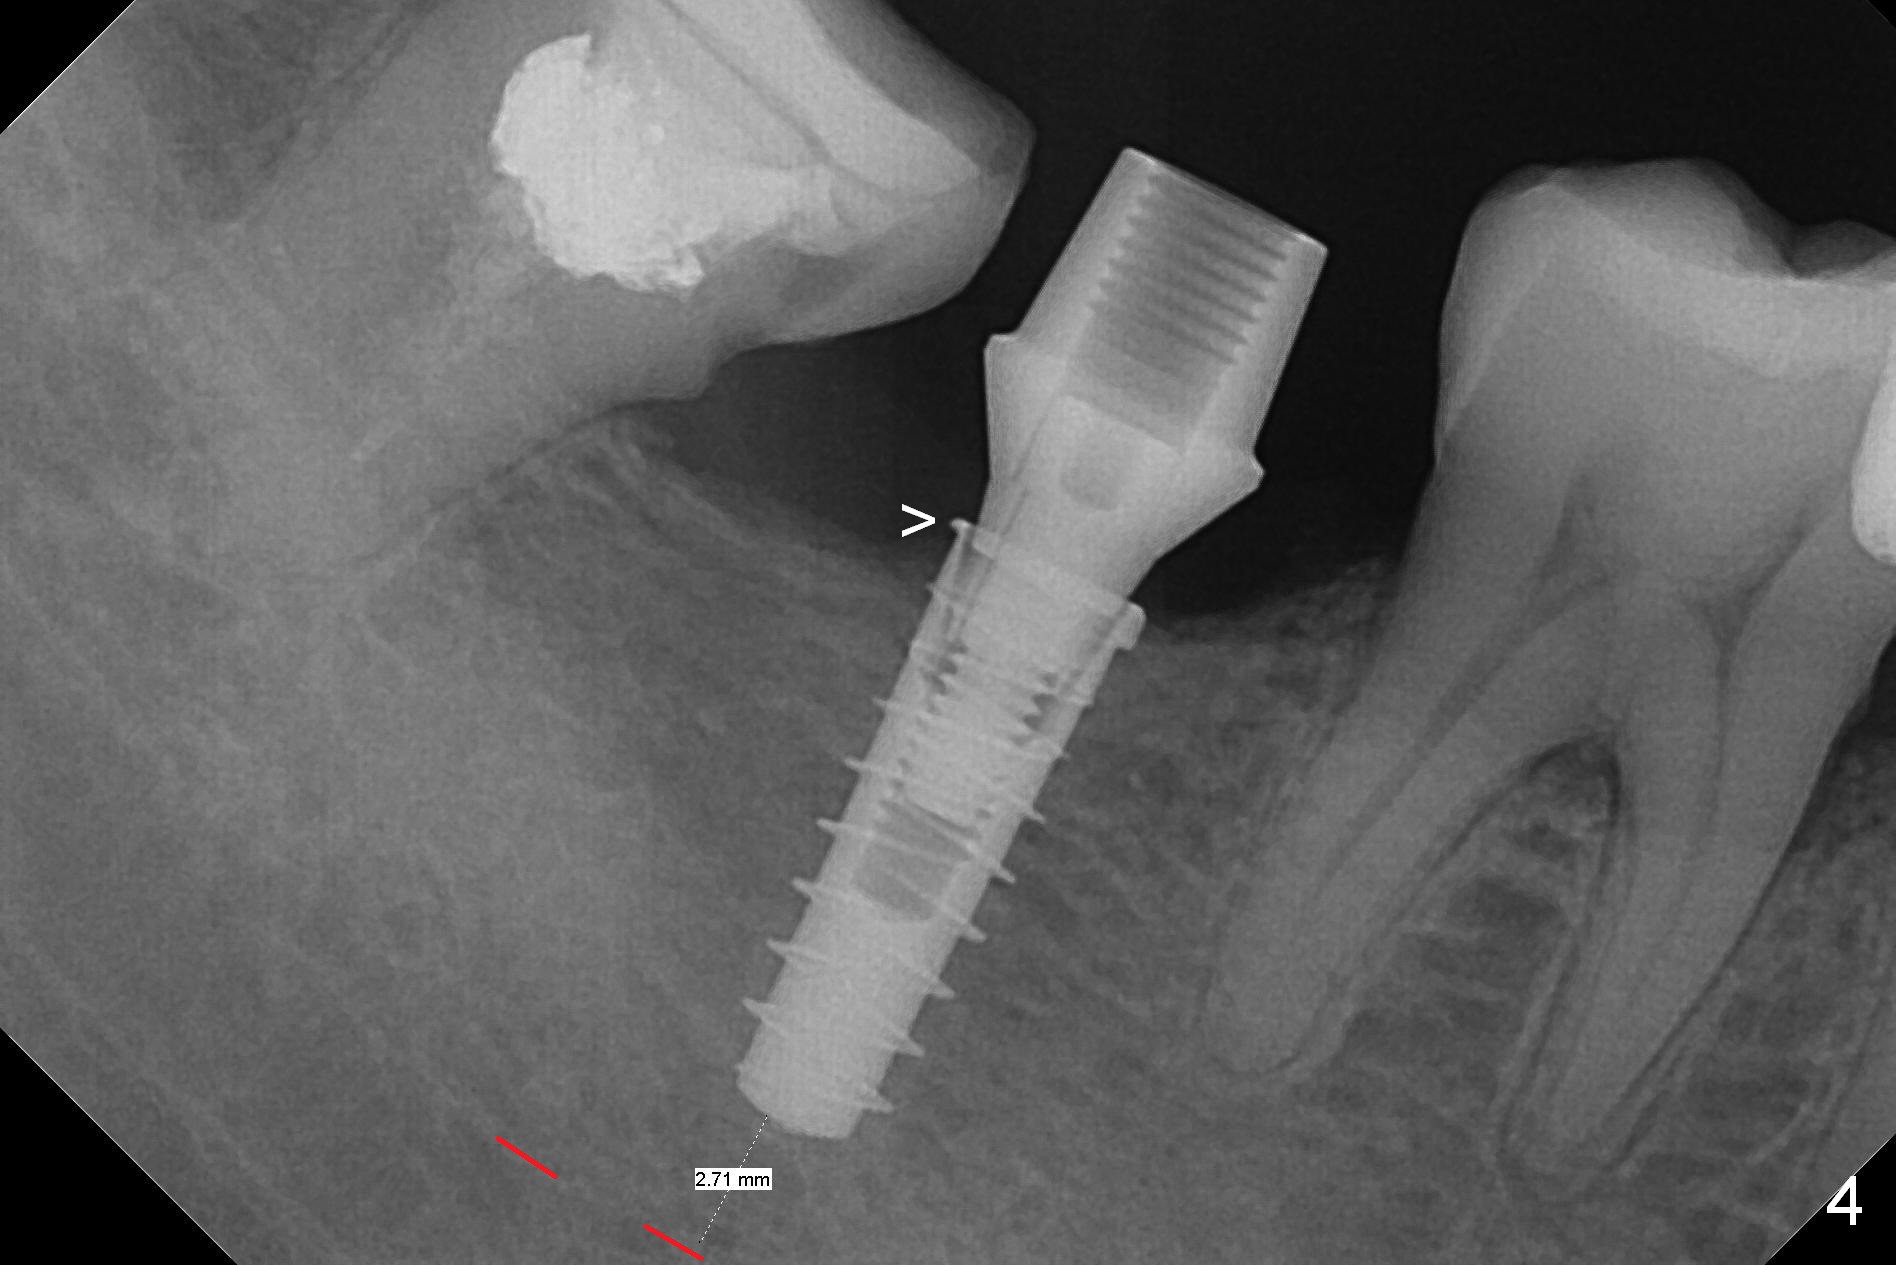

The ridge at #31 is also narrow buccolingually (Fig.1 *). After incision and 1.6 mm pilot drill, a guide pin with 7 mm length is inserted to confirm trajectory and depth; it appears that 11 mm osteotomy has enough clearance from the superior border of the Inferior Alveolar Canal (IAC, Fig.2 red dashed line). Following Marking Bur, 3.3 mm Magic Drill and final drill, the buccal plate seems to be thin (Fig.3 *). When a 4x11 mm IBS implant and 5x4(2) mm pair abutment are placed, the distal thread is exposed (Fig.4 >), the abutment contacts the opposing tooth (data not shown) and there is 2.7 mm clearance from IAC. After increasing the osteotomy 1-2 mm, the implant is placed deeper; the autogenous bone with Osteogen is placed around the plateau of the implant (Fig.5 >), particularly buccally, followed by collagen membrane. When sutures are placed around the abutment, the buccal ridge looks bulkier (Fig.6) than preop (Fig.1). It may remains so long term. The flap surgery makes it possible for simultaneous GBR and reduction in possibility of peri-implantitis. Last, periodontal dressing is applied.